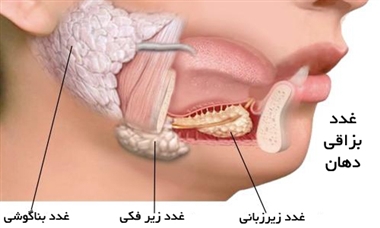

قیمت: 88٬000 تومان - دسته بندی فایل: پاورپوینتپاورپوینت غدد بزاقی

فروش ویژه پاور پوینت حرفه ای غدد بزاقی با تخفیف استثنایی فقط 92 هزار تومان تعداد اسلاید: 54 اسلاید